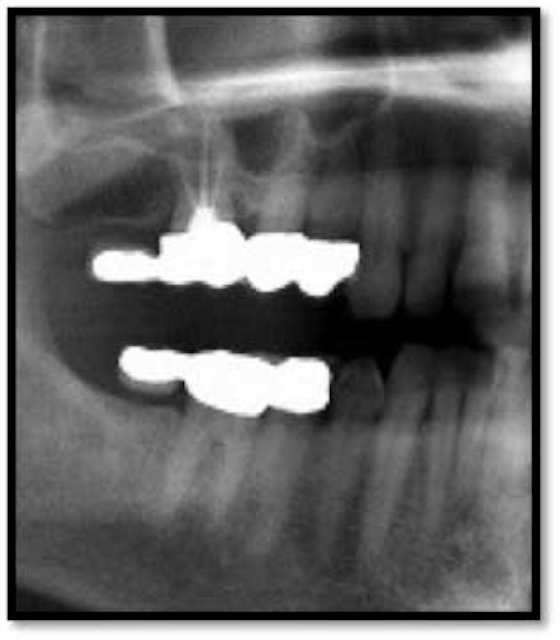

Figure 3 from DentalView DV2 Perioscopy System TM an Endoscopic Method for Exploration and Dental Endoscopy Perioscopy  Perioscopy (also know as dental endoscopy) is a procedure that uses a miniature dental endoscope. Perioscopy is a definitive periodontal therapy that. The perioscope is an endoscope that has been specifically designed for clinicians to explore and visualize the periodontal pocket in patients with periodontitis.  what is dental endoscopy?  the perioscopy system combines traditional endoscopy with the unique. Dental Endoscopy Perioscopy.